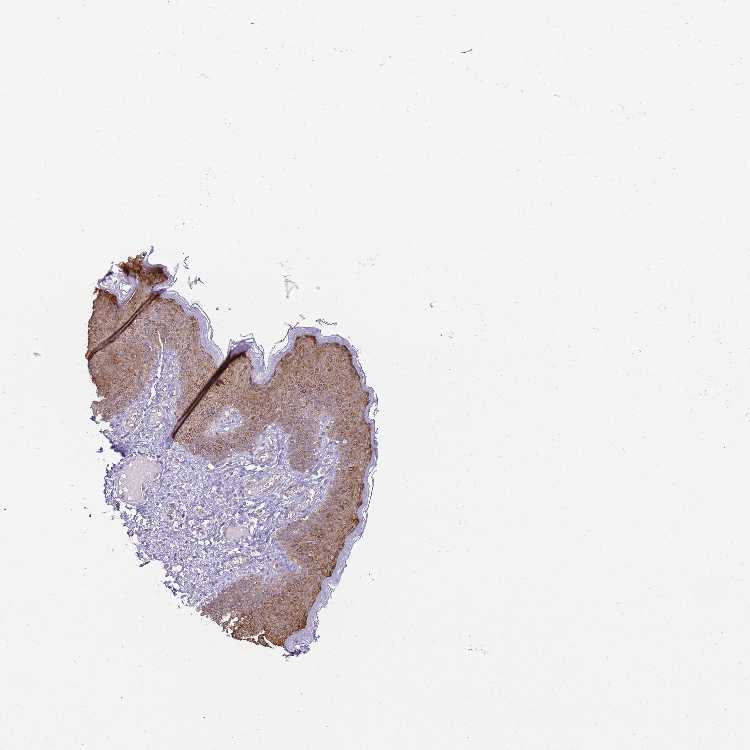

SKIN 1 - Antibody stainingi

Antibody staining in the annotated cell types in the current human tissue is reported as not detected, low, medium, or high, based on conventional immunohistochemistry profiling in selected tissues. This score is based on the combination of the staining intensity and fraction of stained cells.

Each image is clickable and will lead to virtual microscopy that enables deeper exploration of all samples and also displays staining intensity scores, fraction scores and subcellular localization as well as patient and tissue information for each sample.

Antibody HPA000497Antibody CAB004439Antibody CAB047331

Langerhans HighHigh-

Arrector pili muscle cells --Not detected

Cells in basal layer --Medium

Cells in corneal layer --Not detected

Cells in granular layer --Medium

Cells in spinous layer --Medium

Eccrine glands --Medium

Endothelial cells --Low

Extracellular matrix --Not detected

Fibroblasts Not detectedLow-

Fibrohistiocytic cells --Low

Keratinocytes HighHigh-

Langerhans cells --Medium

Lymphocytes --Not detected

Melanocytes MediumHighMedium

Vascular mural cells --Not detected